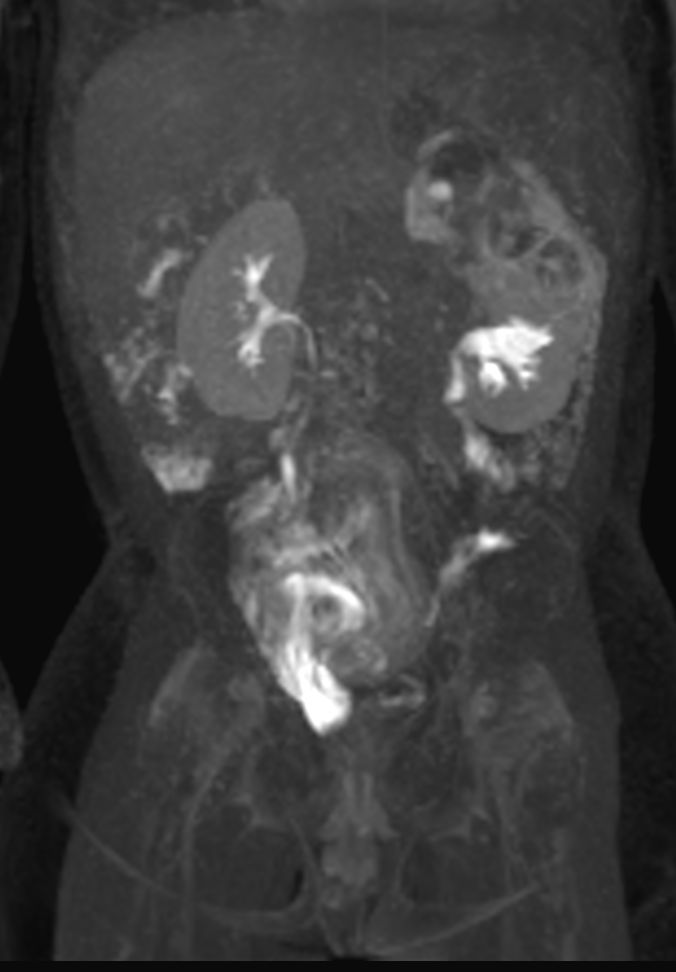

Coronal 3D VIEW T2w SPIR